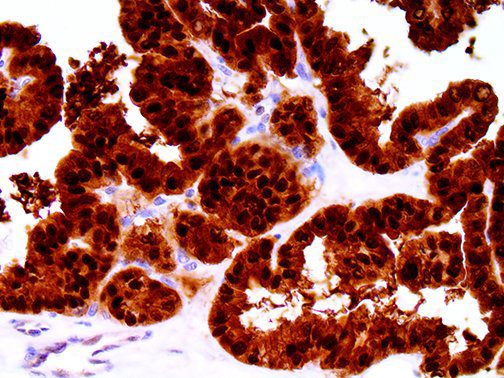

It is the ICU physician who is most likely to witness one of the deadliest manifestations of the abnormal immunological response, the cytokine storm syndrome (CSS). This response is also referred to by some as the cytokine release syndrome (CRS). CSS is characterized by continuous activation and expansion of macrophage and lymphocyte populations, which secrete large amounts of cytokines, causing the cytokine storm. This massive cytokine release is akin to hemophagocytic lymphohistiocytosis (HLH) disease, a syndrome characterized by initial unchecked and persistent activation of cytotoxic T lymphocytes and NK cells.

Clinical and laboratory manifestations of HLH include fever, enlarged liver and/or spleen, neurologic dysfunction, coagulopathy, liver dysfunction, cytopenias (i.e., low levels of erythrocytes, leukocytes, and/or platelets), hypertriglyceridemia, hyperferritinemia, hemophagocytosis, and eventually diminished NK cell activity as the immune system becomes progressively paralyzed. HLH can be familial (primary HLH) or secondary to another disease process (sHLH), such as rheumatic disease, in which it is referred to as macrophage activation syndrome (MAS, characterized by elevated ferritin).